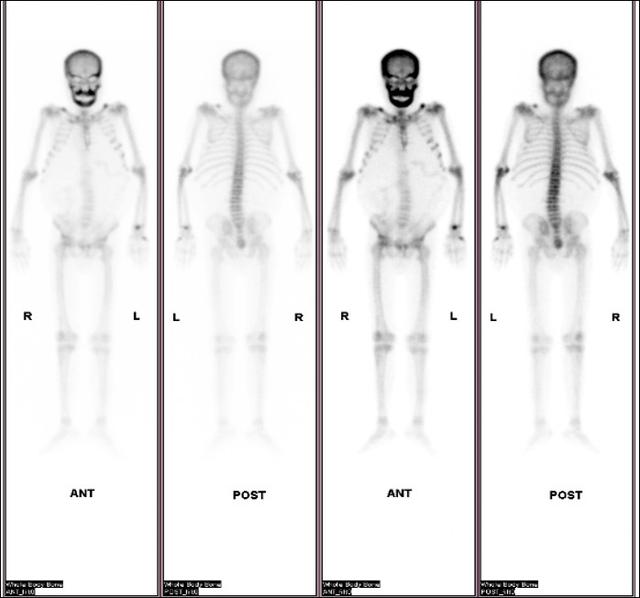

治疗前甲状腺旁腺素非常高(3300pg/ml),血钙正常,超声显示双侧甲状腺旁腺明显增大(如下图),核素扫描显示甲状旁腺功能亢进性骨代谢异常性骨病(骨骼变形)。

介入微创消融治疗时,将功能亢进的甲状旁腺原位灭活(如下图)

介入微创消融治疗后第一天甲状腺旁腺素降为486.2pg/ml(治疗前为3300pg/ml),静脉持续补钙血钙正常